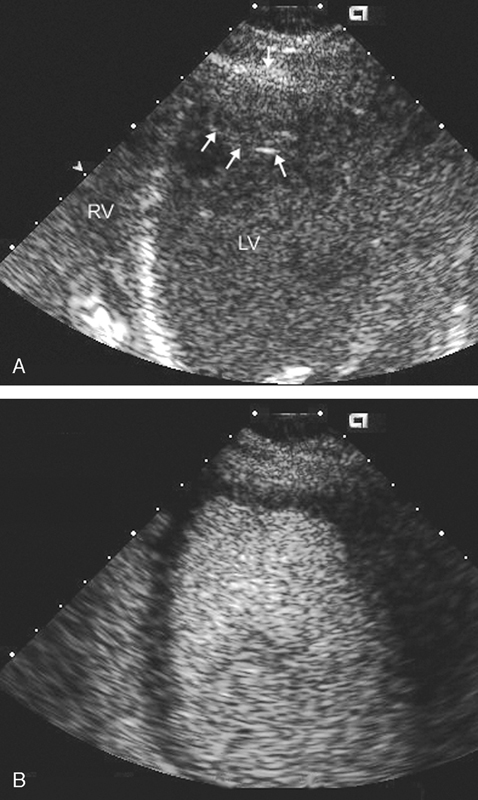

فحوصات تشخيصية لبعض امراض القلب والشرايين التاجية